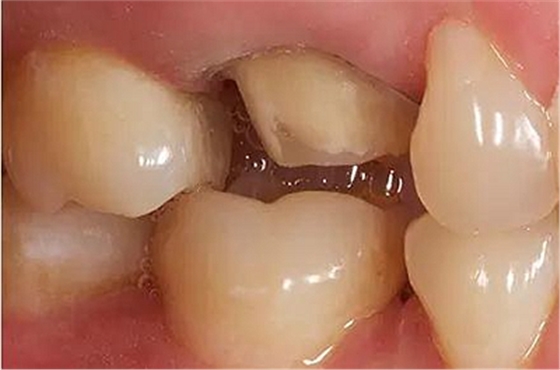

步驟4

咬合間距

與對(duì)牙合牙的咬牙合面間隙至少保留: 1.0 mm 點(diǎn)隙裂溝處的距離,1.5 mm 牙尖高度的距離。